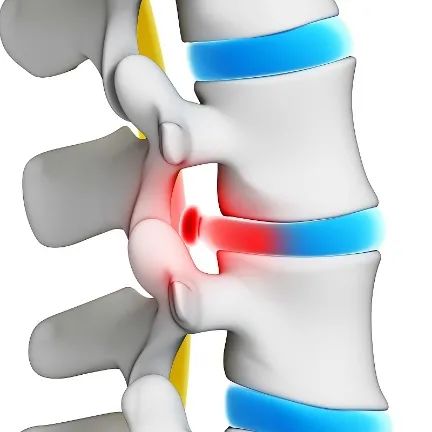

腰痛是怎么引起的?疼痛是神经的异常兴奋引起的。有神经的地方才会疼,没有神经的地方是不会疼的。腰部肌肉常被称为“核心”肌群,是人体发力的主要环节,对上下肢的活动、用力起着承上启下的枢纽作用。人体腰部有五对神经,不同的神经支配腰部及以下的不同部位,临床上可以判断疾病产生的根源。

这个“方子”有保健舒缓的作用,但非治疗手段,是治标不治本的,反而会延误最佳治疗时间。但肌肉或者韧带的扭伤还是管用的,若是腰椎间盘突出肯定是没用的,而且越揉损害越大。腰腿疼还是要找对疼痛的根源,然后对症治疗,有必要可尝试正规的中医正骨治疗方法。

腰腿疼是一个综合性疾病。骨骼、神经、肌肉任何一个部位出了问题,都会造成腰腿疼,拉伸只对肌肉有帮助。网上流行“漫画腰”暗藏着危险和隐患,除非职业需求,否则的话绝对不提倡。因为“漫画腰”的过度拉伸会损害脊柱从前到后的软组织、间盘和小关节等,会增加腰椎退变的风险。